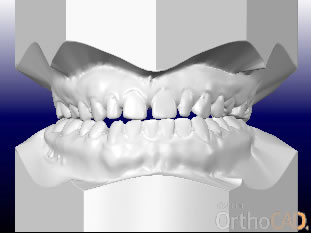

さまざまな問題をふくんでいたので、最新のCAD技術を応用した矯正治療分析ソフトを用いて治療計画を立てて、動画で治療経過予測を説明しています。

こちらに示しているのは治療開始時、手術直前予測、手術後予測の3段階静止画像ですが、実際のCADでは治療経過を動画で表現しています。

正面から見た

治療前、手術前、手術後の予測CAD

右斜めから見た